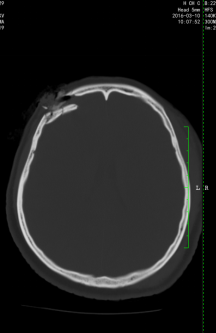

图5(妻子术前CT显示颅骨凹陷粉碎性骨折)

图6 (妻子术后CT显示颅骨骨折整复术后)